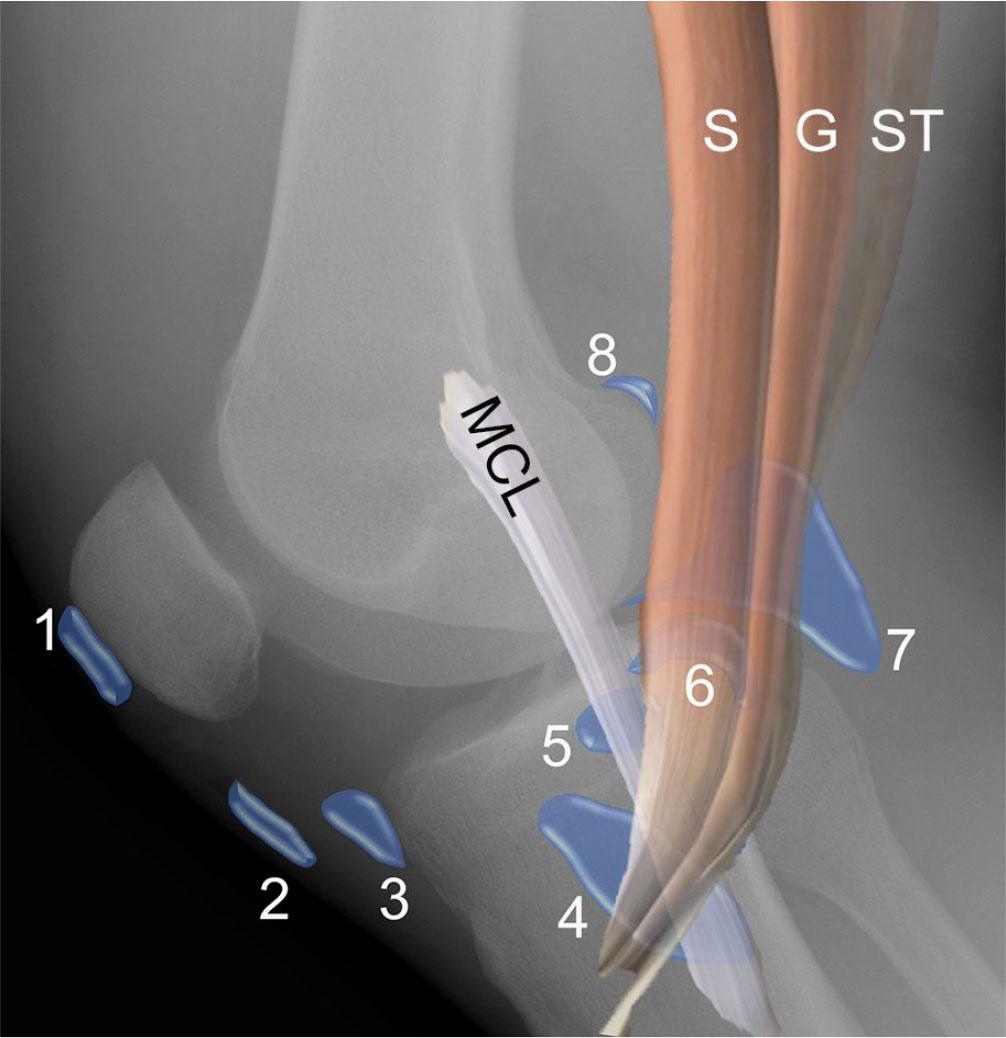

Fig. 9.

Illustrations of medial and lateral supporting structures at the knee joint superimposed on radiographs. A. Illustration of medial collateral ligament (MCL) complex superimposed on PA view of the knee shows the medial meniscal body (1) with deep layer consisting of the attached meniscofemoral and meniscotibial ligaments, middle layer consisting of the tibial collateral ligament (or superficial MCL) (2), with superficial layer composed of crural fascia (3). Note the fibular collateral ligament (4) and popliteus tendon (5) at the lateral knee. B. Illustration of lateral supporting structures, including the iliotibial band (1), fibular collateral ligament (2) running from the femoral condyle to the fibular head and attaching near the biceps femoris (BF) tendon insertion, as well as the posterolateral corner structures consisting of the popliteofibular ligament (3) arising from the fibular styloid and attaching to the popliteus (P) myotendinous junction, the Y-shaped arcuate ligament (4), and the fabellofibular ligament (5)

Additional lateral supporting structures include the popliteus muscle and tendon, biceps femoris tendon, as well as the popliteofibular, arcuate and fabellofibular ligaments (Fig. 9 B). Along with the joint capsule and lateral patellar retinaculum, the lateral gastrocnemius tendon and iliotibial tract provide additional lateral stabilization. MRI allows for a rapid comprehensive assessment of these numerous structures, particularly in the setting of acute multiligamentous injury(30).